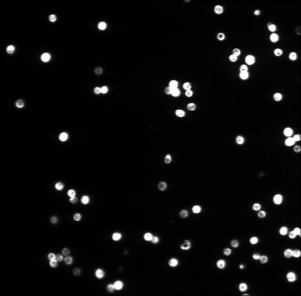

In Figure 14 (a), (d), (g) and (j) experimental data sets are shown. From the original image sets, consisting of three different fluorescent color channels, we extracted the tumor cell marker (green) and used those images as input for our multiscale segmentation approach. Although the difficulties vary between all images (inhomogeneous background, noise, cell clusters, mixture of size and intensity scales), we can process all images with our multiscale segmentation approach with the exact same parameters. This is essential for the development of a user-friendly (parameter-free) toolbox for CTC analysis. Note that the dim spots in image (d) are not cells but only pores of a filter used to collect cells (bright spots) and therefore it is not desired to segment them. The resulting spectral response functions for all four images are shown in Figure 14 (b), (e), (h) and (k) with a color coding corresponding to the coding used in the segmentation results in (c), (f), (i) and (l). The color coding of the response function shows that all objects which appear later in our segmentation and therefore belong to finer scales have a yellow to reddish color in the color-coded segmentation. The very large and intact cells are blue (with some small artifacts at the boundary) and smaller cells (or large fragments) are shown in light blue to green. We can nicely observe that the object colors cover the whole color scale range. For images that are more complex (e.g. (d) and (j)) also the spectral response function is more complex but the color-coded segmentation shows that nearly every object appears in one step and thereby has a clearly defined scale that we use as a feature in our classification approach. Here, we profit from the fact that not only Wulff shapes (perfectly circular objects) but also other eigenshapes appear in one step in our segmentation. Hence, this segmentation approach not only provides all contours automatically without any parameter adaptations but simultaneously also a simple classification of cells based on their size (scale resp. color/appearance time). This analysis can be applied to all color channels separately and be used together with more features in a subsequent automatic classification approach. The constants and can again simply be estimated a-priori from the data by a simple thresholding and averaging approach and are fixed throughout the iterative process.